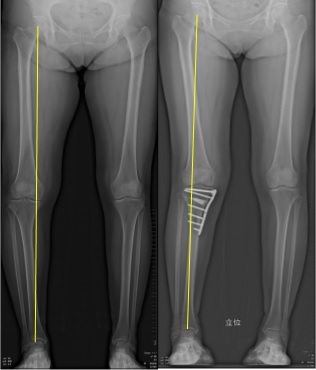

股関節の中心と足首の中心を結んだ体重の通る線が、膝関節の中央よりも内側によっている方は、膝関節の内側だけに負担が集中しています(いわゆるO脚)。ここのような方は、クッションの役割をする半月板の損傷などをきっかけに、内側の軟骨がすり減り、変形が進みやすいことが知られています。足の装具(足底板)やヒアルロン酸注射などによる保存療法を行なうこともありますが、患者さんと相談して下記の図のように、骨を切り、下肢全体の並びを整え、体重のかかる位置をずらします。人工関節を使用しないため、自分の関節が温存出来ることが最大の特徴でありメリットです。骨が癒合したら金属の板を抜去します。(術後約1~2年後)

股関節と足関節の中心を結んだ線(荷重軸)

術前は膝関節の内側を通っています(左)。

術後は膝関節の外側を通るようになっており、内側の負担が減り、痛みが改善します。(右)

術前は膝関節の内側を通っています(左)

術後は膝関節の中央を通るようになっており、見た目にも足がまっすぐになります。(右)